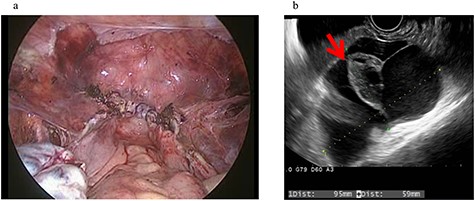

Four years and 6 months after surgery, she presented with lower left abdominal pain. A multilocular cyst, measuring ~10 cm, was detected on the vaginal stump by transvaginal US (Fig. 2b). Since the cyst was considered to be causing her symptoms, emergency surgery was performed. Adhesions were observed in the left adnexal region, and a clear yellow liquid was retained in the cavity formed by the adhesions (Fig. 3). The adhesions were removed by laparoscopic surgery and left adnexal excision was performed, which ameliorated her symptoms.

Clinical findings of case 2 (during surgery for PIC). (a) Strong adhesion between the sigmoid colon and pelvic wall in the left adnexal region. (b) When the sigmoid mesentery and left pelvic peritoneum were removed and the cyst was opened, a yellow transparent liquid was ejected. (c) The cavity formed by adhesions. (d) Left ovarian tissue inside PIC.